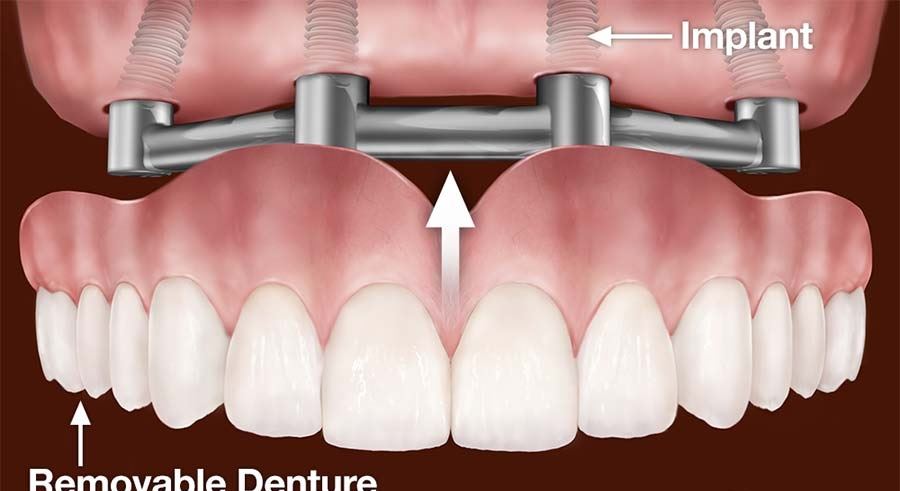

A dental implant is a surgical component that interfaces with the bone of the jaw or skull to support a dental prosthesis such as a crown, bridge, denture, or facial prosthesis. Essentially, dental implants act as artificial roots for replacement teeth.

The typical structure of a dental implant consists of three main parts:

The Implant Post: Usually made of titanium, this is the part that is surgically placed into the jawbone. Titanium is biocompatible, meaning it is accepted by the body and integrates well with bone.

The Abutment: This is a connector placed on top of the dental implant to hold and support a tooth or set of teeth.

The Crown: The visible part of the tooth, typically made of porcelain or ceramic, which is attached to the abutment.